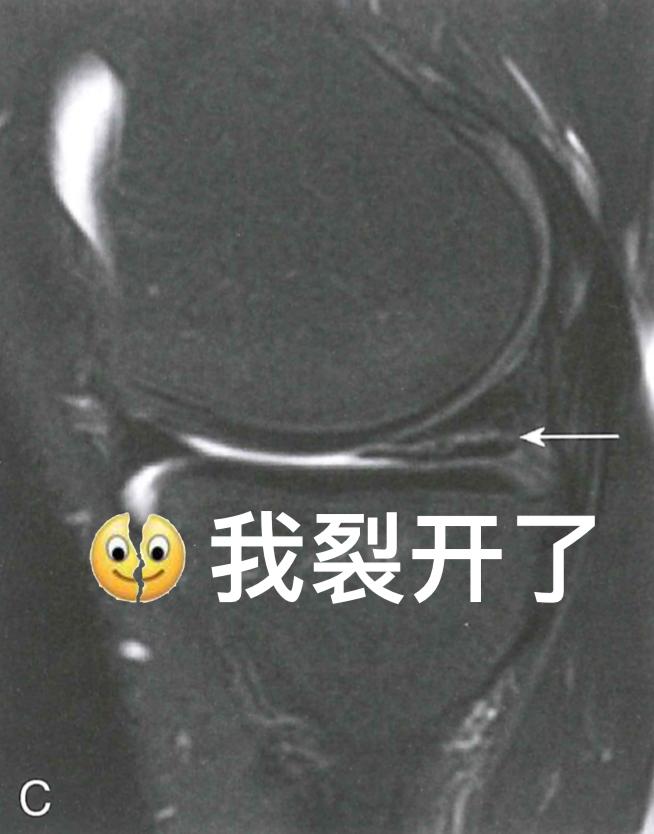

除了韧带可能在运动中被扯断、撞坏之外,膝关节里还有两块半月板也很容易受伤。就像坐在硬板凳上屁股硌得难受一样,膝关节上下两个大骨头要是直接硬碰硬,你的膝关节肯定不会好受。而半月板就像两块缓冲垫,能让股骨和胫骨和谐共处,你的膝关节也能正常发挥功能。不过,如果半月板出现了损伤,那你的膝关节可能就不会那么灵活,蹲下站起可能会“咔咔”响,甚至有时好像卡住了一样。这时,MRI也是诊断的重要工具,如果真的存在半月板撕裂,在膝关节MRI上就能看到半月板“裂开”了。